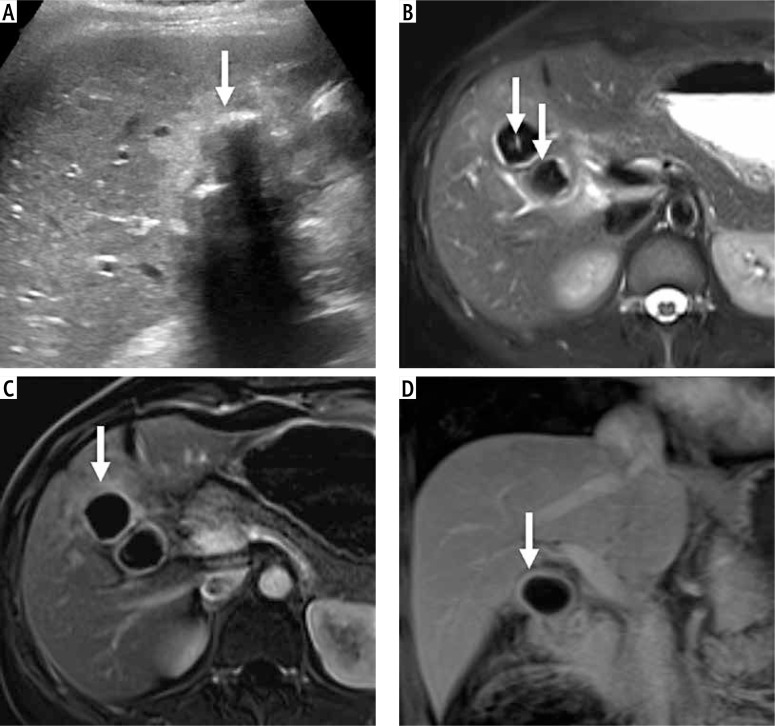

Material and methods: Consecutive patients with non-diagnostic US due to calculi within the gallbladder lumen, obscuring the detailed evaluation, were identified by a research fellow from a prospective database of patients with gallbladder lesions. The US reports and images were evaluated by a radiologist blinded to the final diagnosis. Patients who had the final pathological diagnosis based on fine-needle aspiration cytology, percutaneous or endoscopic biopsy, or surgical histopathology were included. Convolution neural networks (ResNet50, GBCNet), transformer models (vision transformer [ViT], RadFormer), and a hybrid model (MedViT) were trained on a public gallbladder dataset (GBCU dataset). The performance of these models for classifying gallbladder lesions into benign and malignant was tested on non-diagnostic (GB-RADS 0) US images.

Results: Training and validation cohorts (GBCU dataset) comprised 1004 and 251 images, respectively. The testing data (26 patients, mean age [SD]: 57.5 ±8.07 years, 17 female) comprised 304 images. The best performance for detection of GBC was achieved with GBCNet (sensitivity 51.1%, specificity 83.3%, area under the curve [AUC] 0.709) and MedViT (sensitivity 92.8%, specificity 50%, AUC 0.714). MedViT had the best accuracy (73.1%) for detecting benign gallbladder lesions.